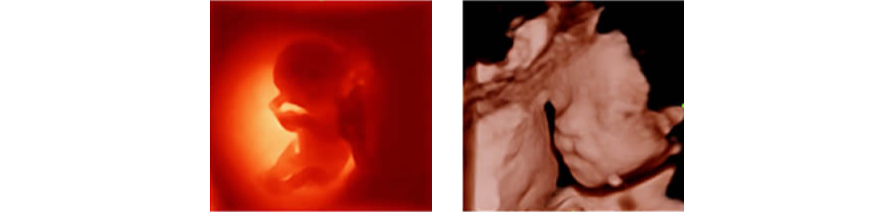

Al integrar un algoritmo de proyecciÃģn de rayos con una nueva modalidad de iluminaciÃģn virtual, iLive genera imÃĄgenes increÃblemente reales del feto con una piel de apariencia humana.

El nuevo Z50 proporciona una optimizaciÃģn rÃĄpida e inteligente del rostro del feto con una simple operaciÃģn de un solo toque. Puede eliminar de forma inmediata las oclusiones en los datos de volumen, excluir el ruido no deseado y generar una visiÃģn Ãģptima del rostro fetal con un mÃnimo de esfuerzo.